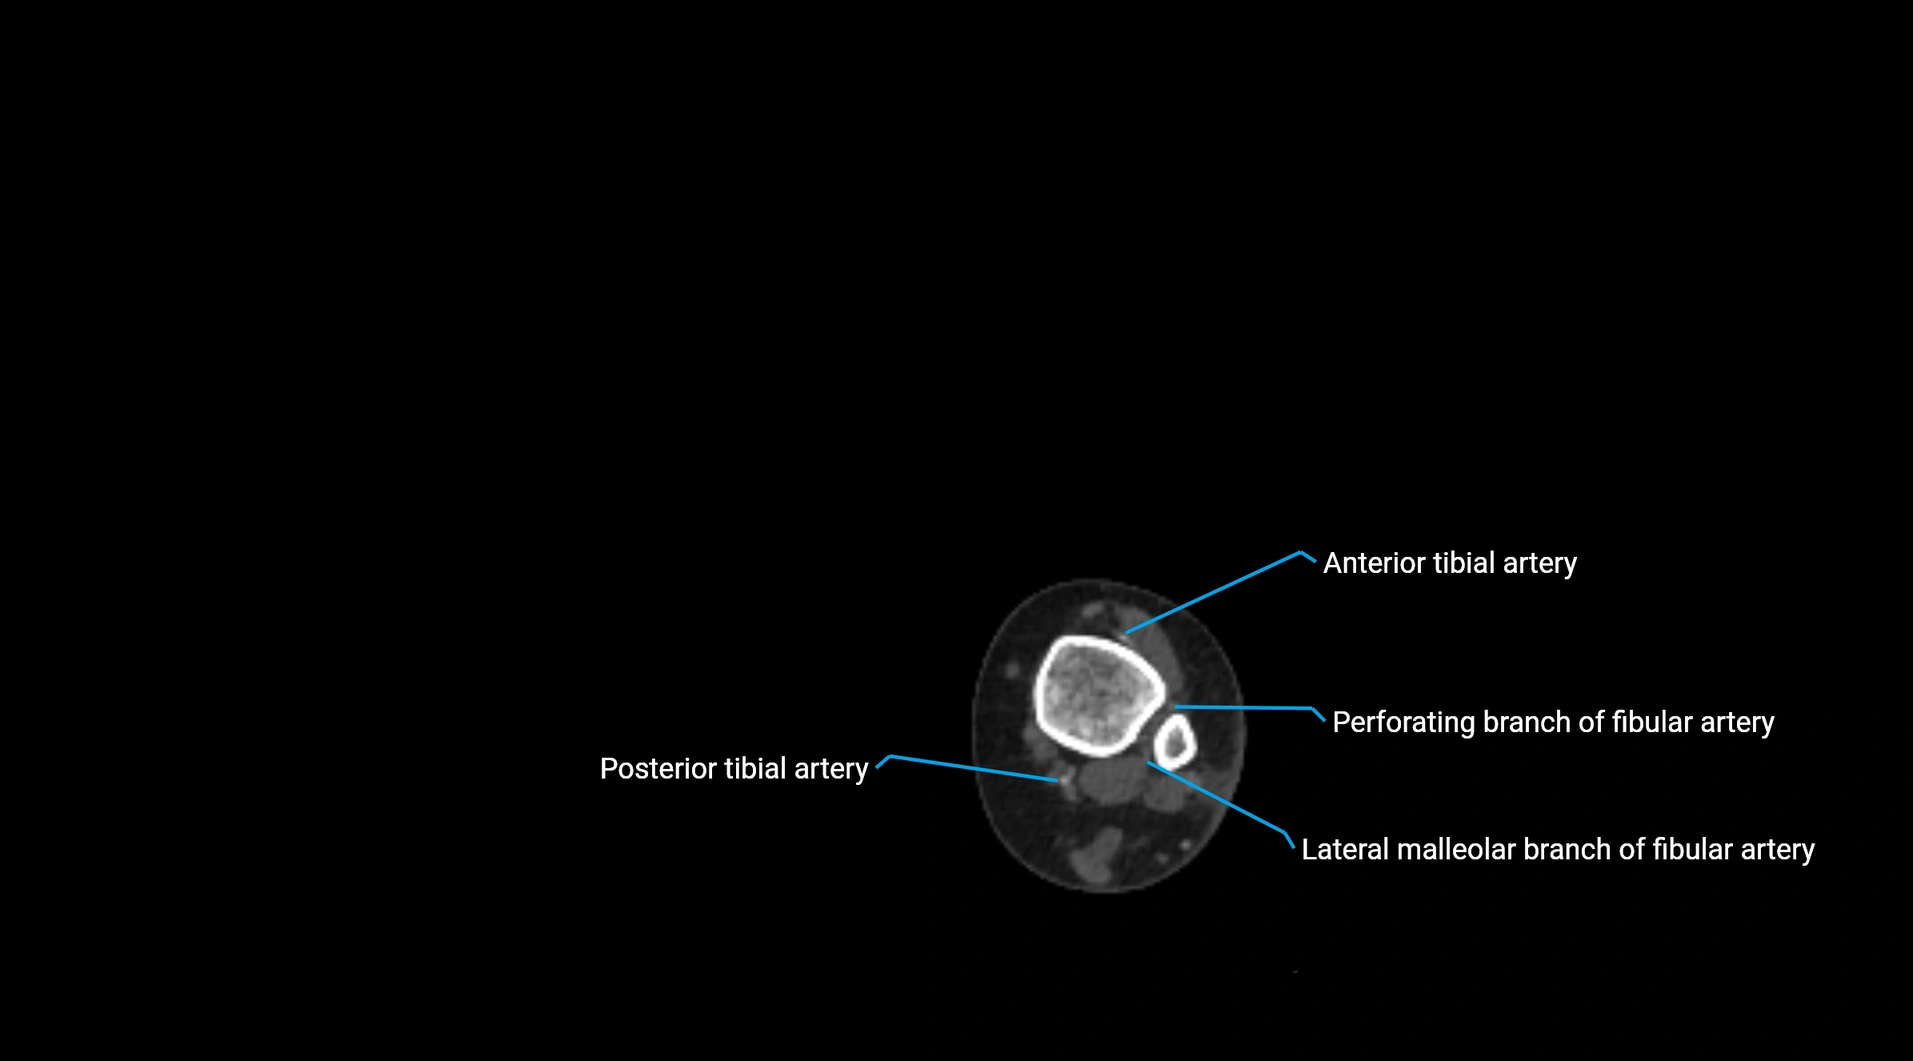

Contrast-enhanced CT (CTA):

• Gold standard for abdominal aortic imaging

• Provides excellent detail of lumen, wall, aneurysm, thrombus, and branch vessels

• Multiplanar and 3D reconstructions help in aneurysm measurement, stent graft planning, and dissection evaluation

• Detects acute rupture, traumatic injury, or occlusion with high sensitivity